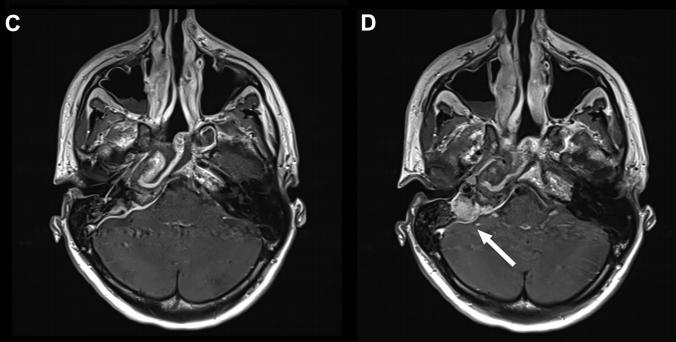

▼术后 (C、D) 图像显示病灶次全切除,并显示鼻中隔瓣修复良好。显示岩尖最后面的小部分残留病灶(C、D、箭头)。值得注意的是,除了鼻中隔后三分之二和蝶窦外,所有其他鼻内正常组织结构均被保留完整无损。